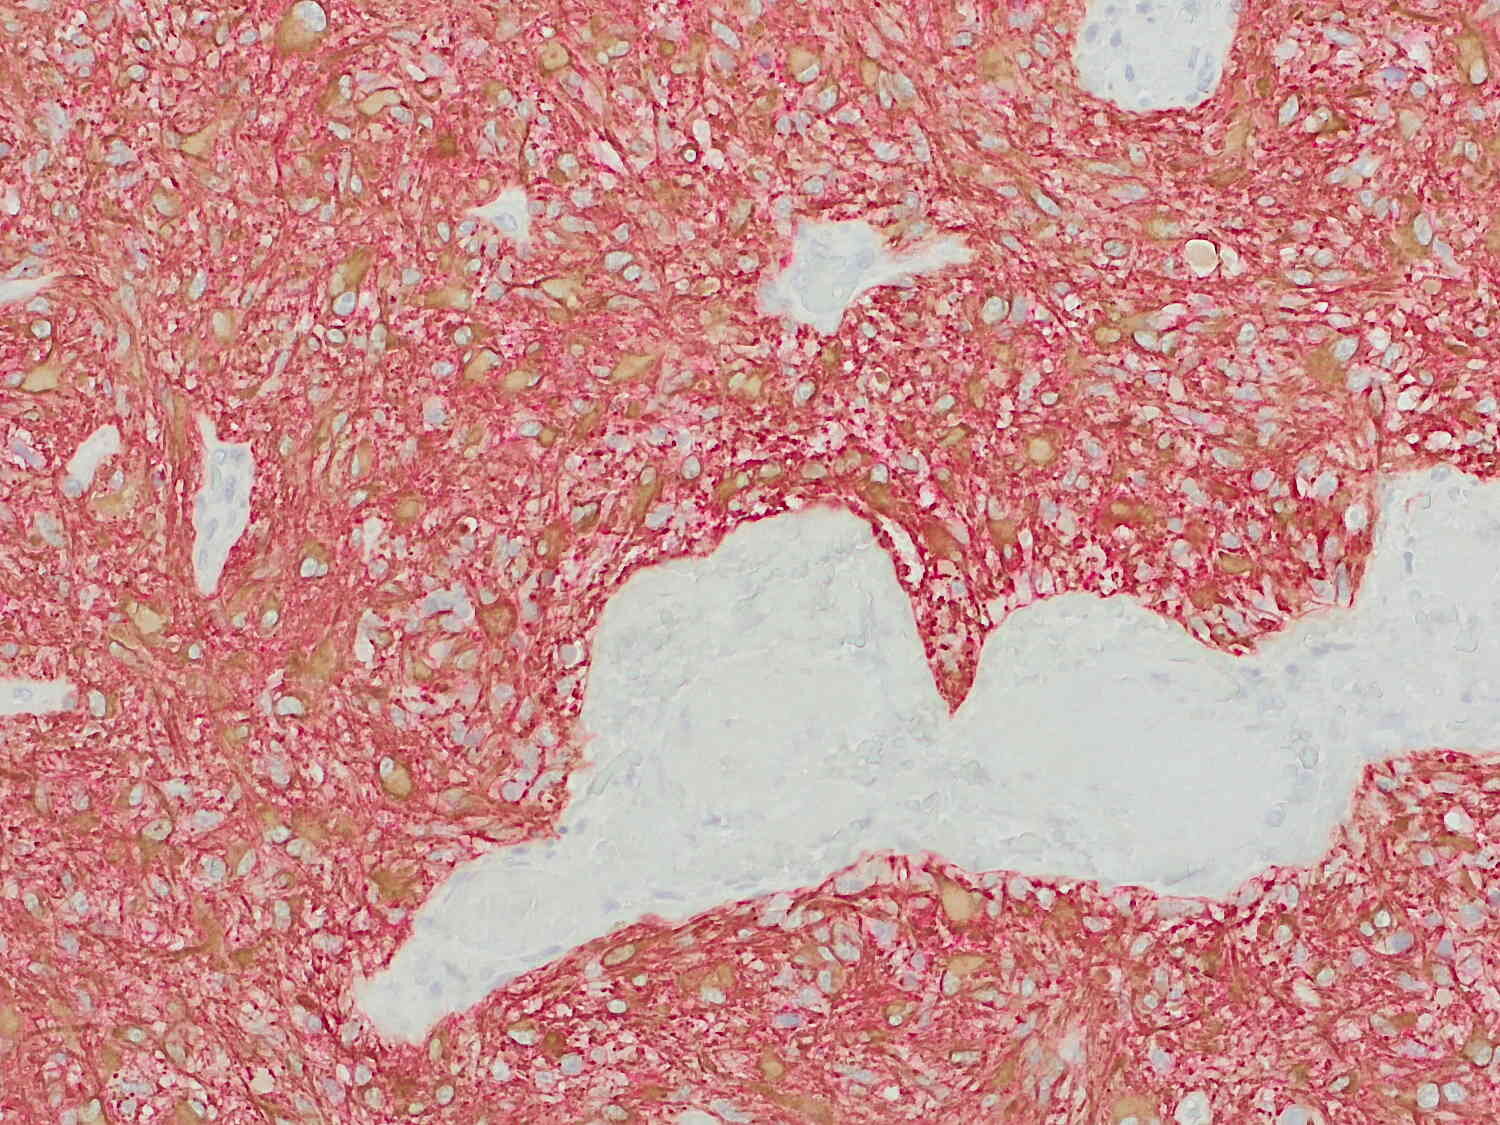

Applications | |

Aquaporin4, or AQP4, also known as Mercurial-insensitive water channel (MIWC), is a member of the aquaporin water channel family. This osmoreceptor regulates body water balance and mediates water flow within the central nervous system.